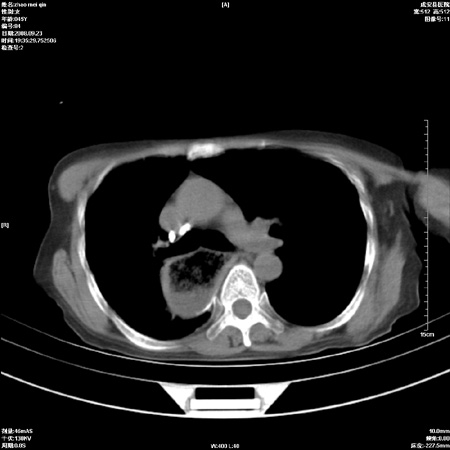

标题: CT15861:女 60 外伤后1小时 胸疼 [打印本页]

标题: CT15861:女 60 外伤后1小时 胸疼

外伤后1小时 胸疼 是外伤后引起的吗?

食道扩张明显下端逐渐变窄,倒像贲门失迟缓

未除外食道异物。如食道石长时间受阻。

不除外贲门占位梗阻

非外伤性改变,典型的贲门失迟缓症

食道扩张明显下端逐渐变窄,大量食物存留,象贲门失迟缓症。